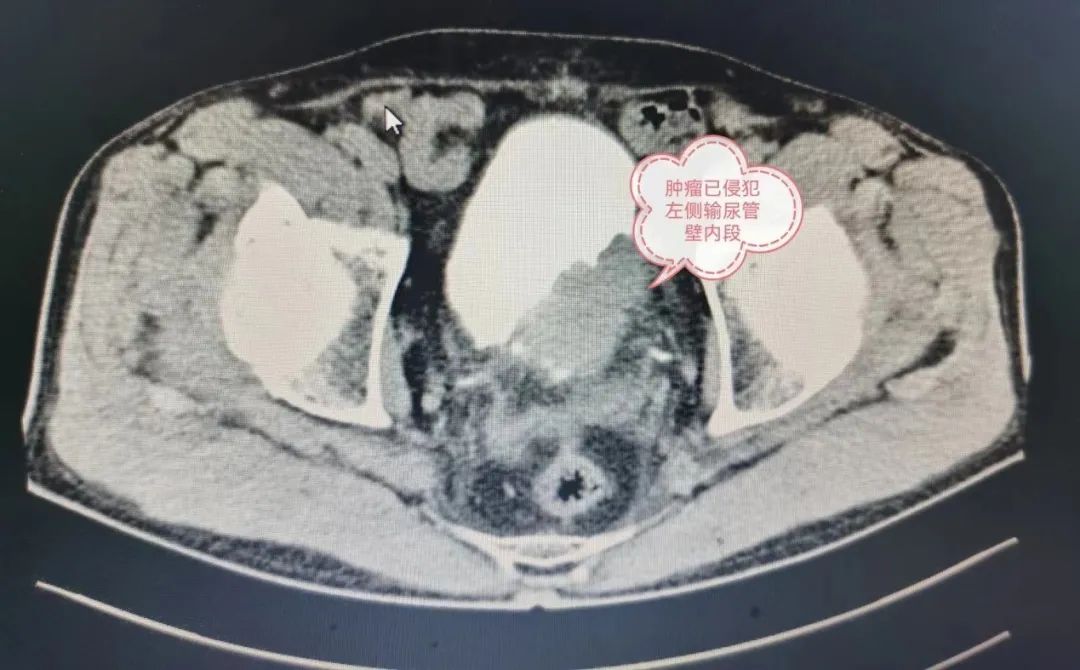

因舒大爷年龄偏高、肿瘤分期较晚、与周围组织粘连严重、合并严重心律不齐伴阿-斯综合征(最慢心率 29 次/分钟、最快心率 198 次/分),术前由心内科介入导管室安置心脏临时起搏器;由董永超主任主刀的泌尿外科团队,术中通过降低气腹压减少对心肺功能的影响,以腹腔镜微创技术完整切除病变、降低对周围组织器官的干扰、减少出血;经过四个小时的精细操作,手术顺利完成。

膀胱癌是我国泌尿外科最常见的肿瘤之一,占男性全身恶性肿瘤第七位,目前腹腔镜下膀胱根治性切除+盆腔淋巴结清扫是国内开展最多的手术方式。该手术涉及组织器官达 13 种,手术难度大、步骤繁琐、耗时长,是泌尿外科的标志性手术。

「患者膀胱切除和盆腔淋巴清扫术后,通过取一段回肠来代替膀胱的存尿功能,然后将双侧输尿管吻合到回肠上,由于患者现在无法再用原先的尿道,通过在小腹部体外造瘘外接尿袋进行了尿流改道。虽然患者相对后期生活比较麻烦一点,但从疾病和生命的角度来说,这不算什么了。」 董永超主任介绍了该手术的方式。